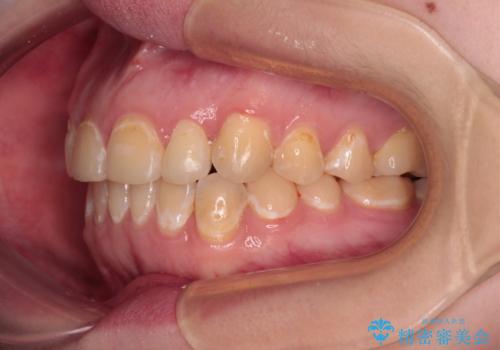

- 前歯のデコボコとクロスバイトが気になり、インビザラインによる矯正治療を希望して来院された患者様です。

上顎側切歯(上の真ん中から2番目の歯)が舌側転位している場合、無理して動かそうとすると歯髄壊死を起こすリスクが高い印象があります。

インビザライン単体でも治療は可能ですが、安全策としてインビザラインで歯列を移動する前に上顎前歯をワイヤー矯正で整え、その後上下歯列をインビザラインにて矯正治療を行うこととしました。

舌側転位している側切歯特有の、切縁の位置が不揃いであったり、根元が内側に引っ込んだ状態であったりという、インビザライン独特の仕上がりになることなく、きれいに整った歯列とすることができました。